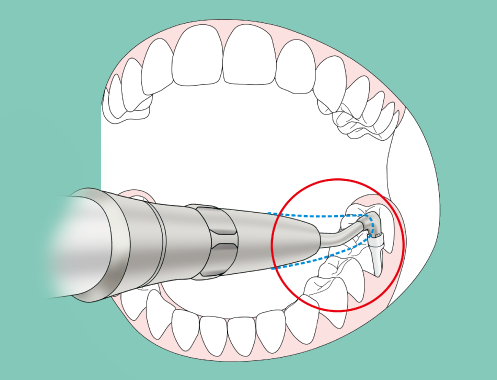

The slim nozzle tip possesses just the right degree of flexibility to pass smoothly over tooth surfaces, and can be easily inserted into tight pockets and the root surfaces of adjacent teeth without causing the patient discomfort.

The long, narrow nozzle shape is designed to allow easy access to areas that require inserting the handpiece at an angle, such as between molars.